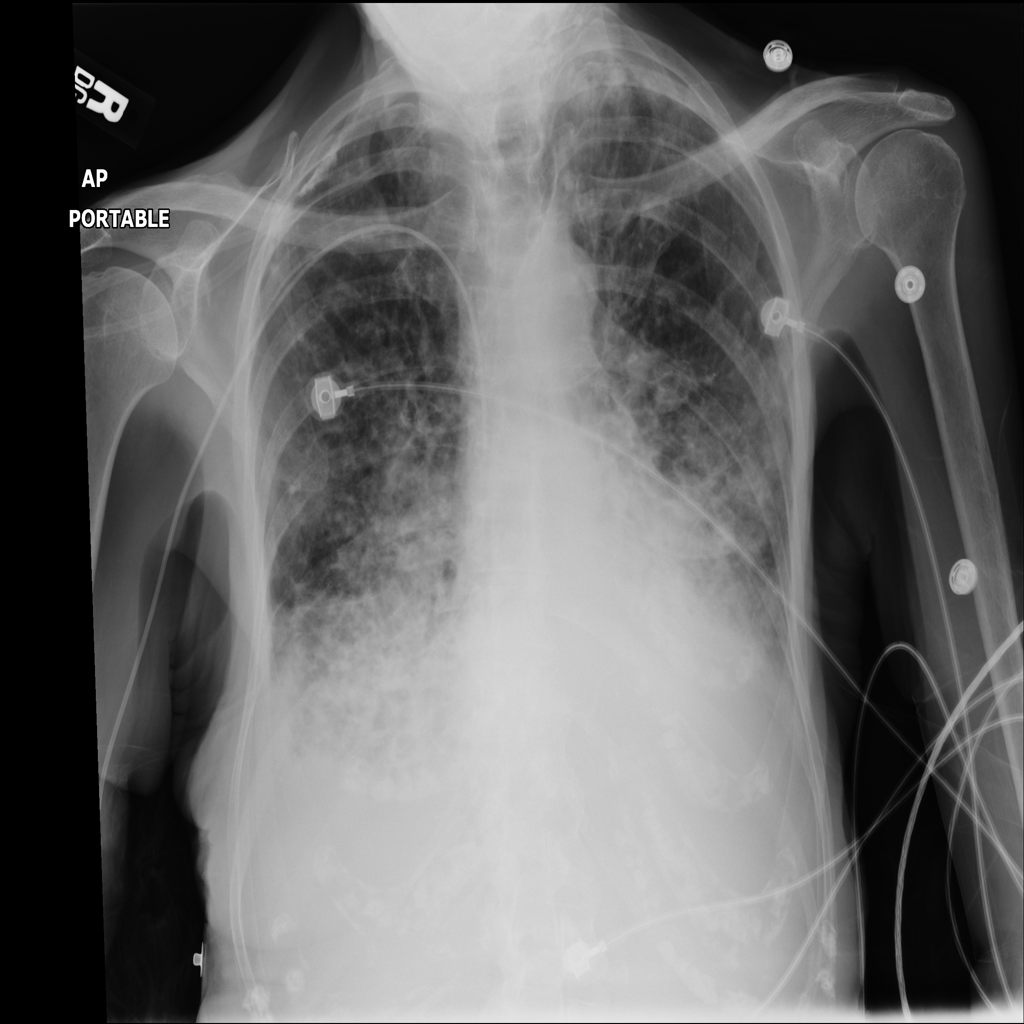

Consolidation

Consolidation refers to air-space filling that makes part of the lung appear denser on imaging.

Showing up to 90 reference images for Consolidation.

PAT-B733 · IMG-000Consolidation

PAT-B733 · IMG-000

PA